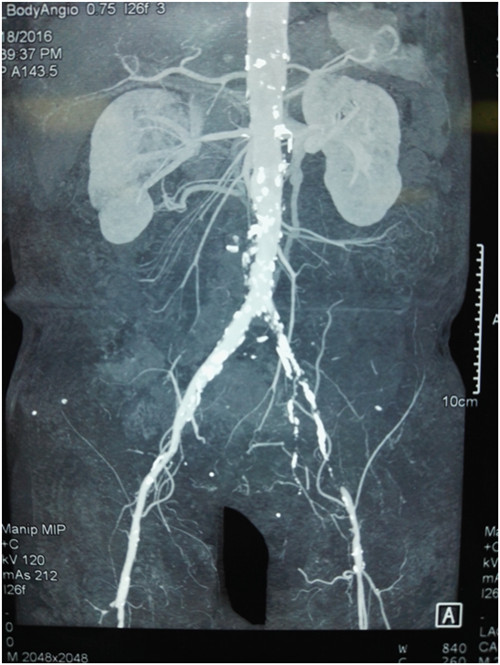

入院后检查,心功能差,肺功能差,低蛋白血症。血管超声提示:左下肢动脉粥样硬化斑块形成并部分血管狭窄,左下肢肌间静脉血栓。我院颈部血管CTA提示左颈总动脉狭窄,左侧椎动脉不显影,左侧锁骨下动脉壁毛糙;腹部CTA提示左侧髂股动脉闭塞段长约14.6cm。经科室讨论,考虑患者年龄大,心肺功能不好,不能耐受全麻血管旁路手术,考虑行局麻下血管腔内手术。

经术前1周精心准备,在科室陈熹主任的统筹协调下,于4月25日下午局麻下在我院介入手术室由普外科马建仓副教授,李宗禹医师在介入室张尚军主管技师配合下完成了普外科首例髂股动脉长段闭塞球囊扩张、支架植入术。术中造影证实左侧髂股动脉闭塞,通过翻山技术从右侧股动脉穿刺入路,导丝顺利通过狭窄病变,球囊扩张后,置入网状支架,使得血管通畅。术后给予双抗,患者静息痛明显改善,换药创面分泌物明显减少,休息明显好转。患者现在正在平稳恢复中。